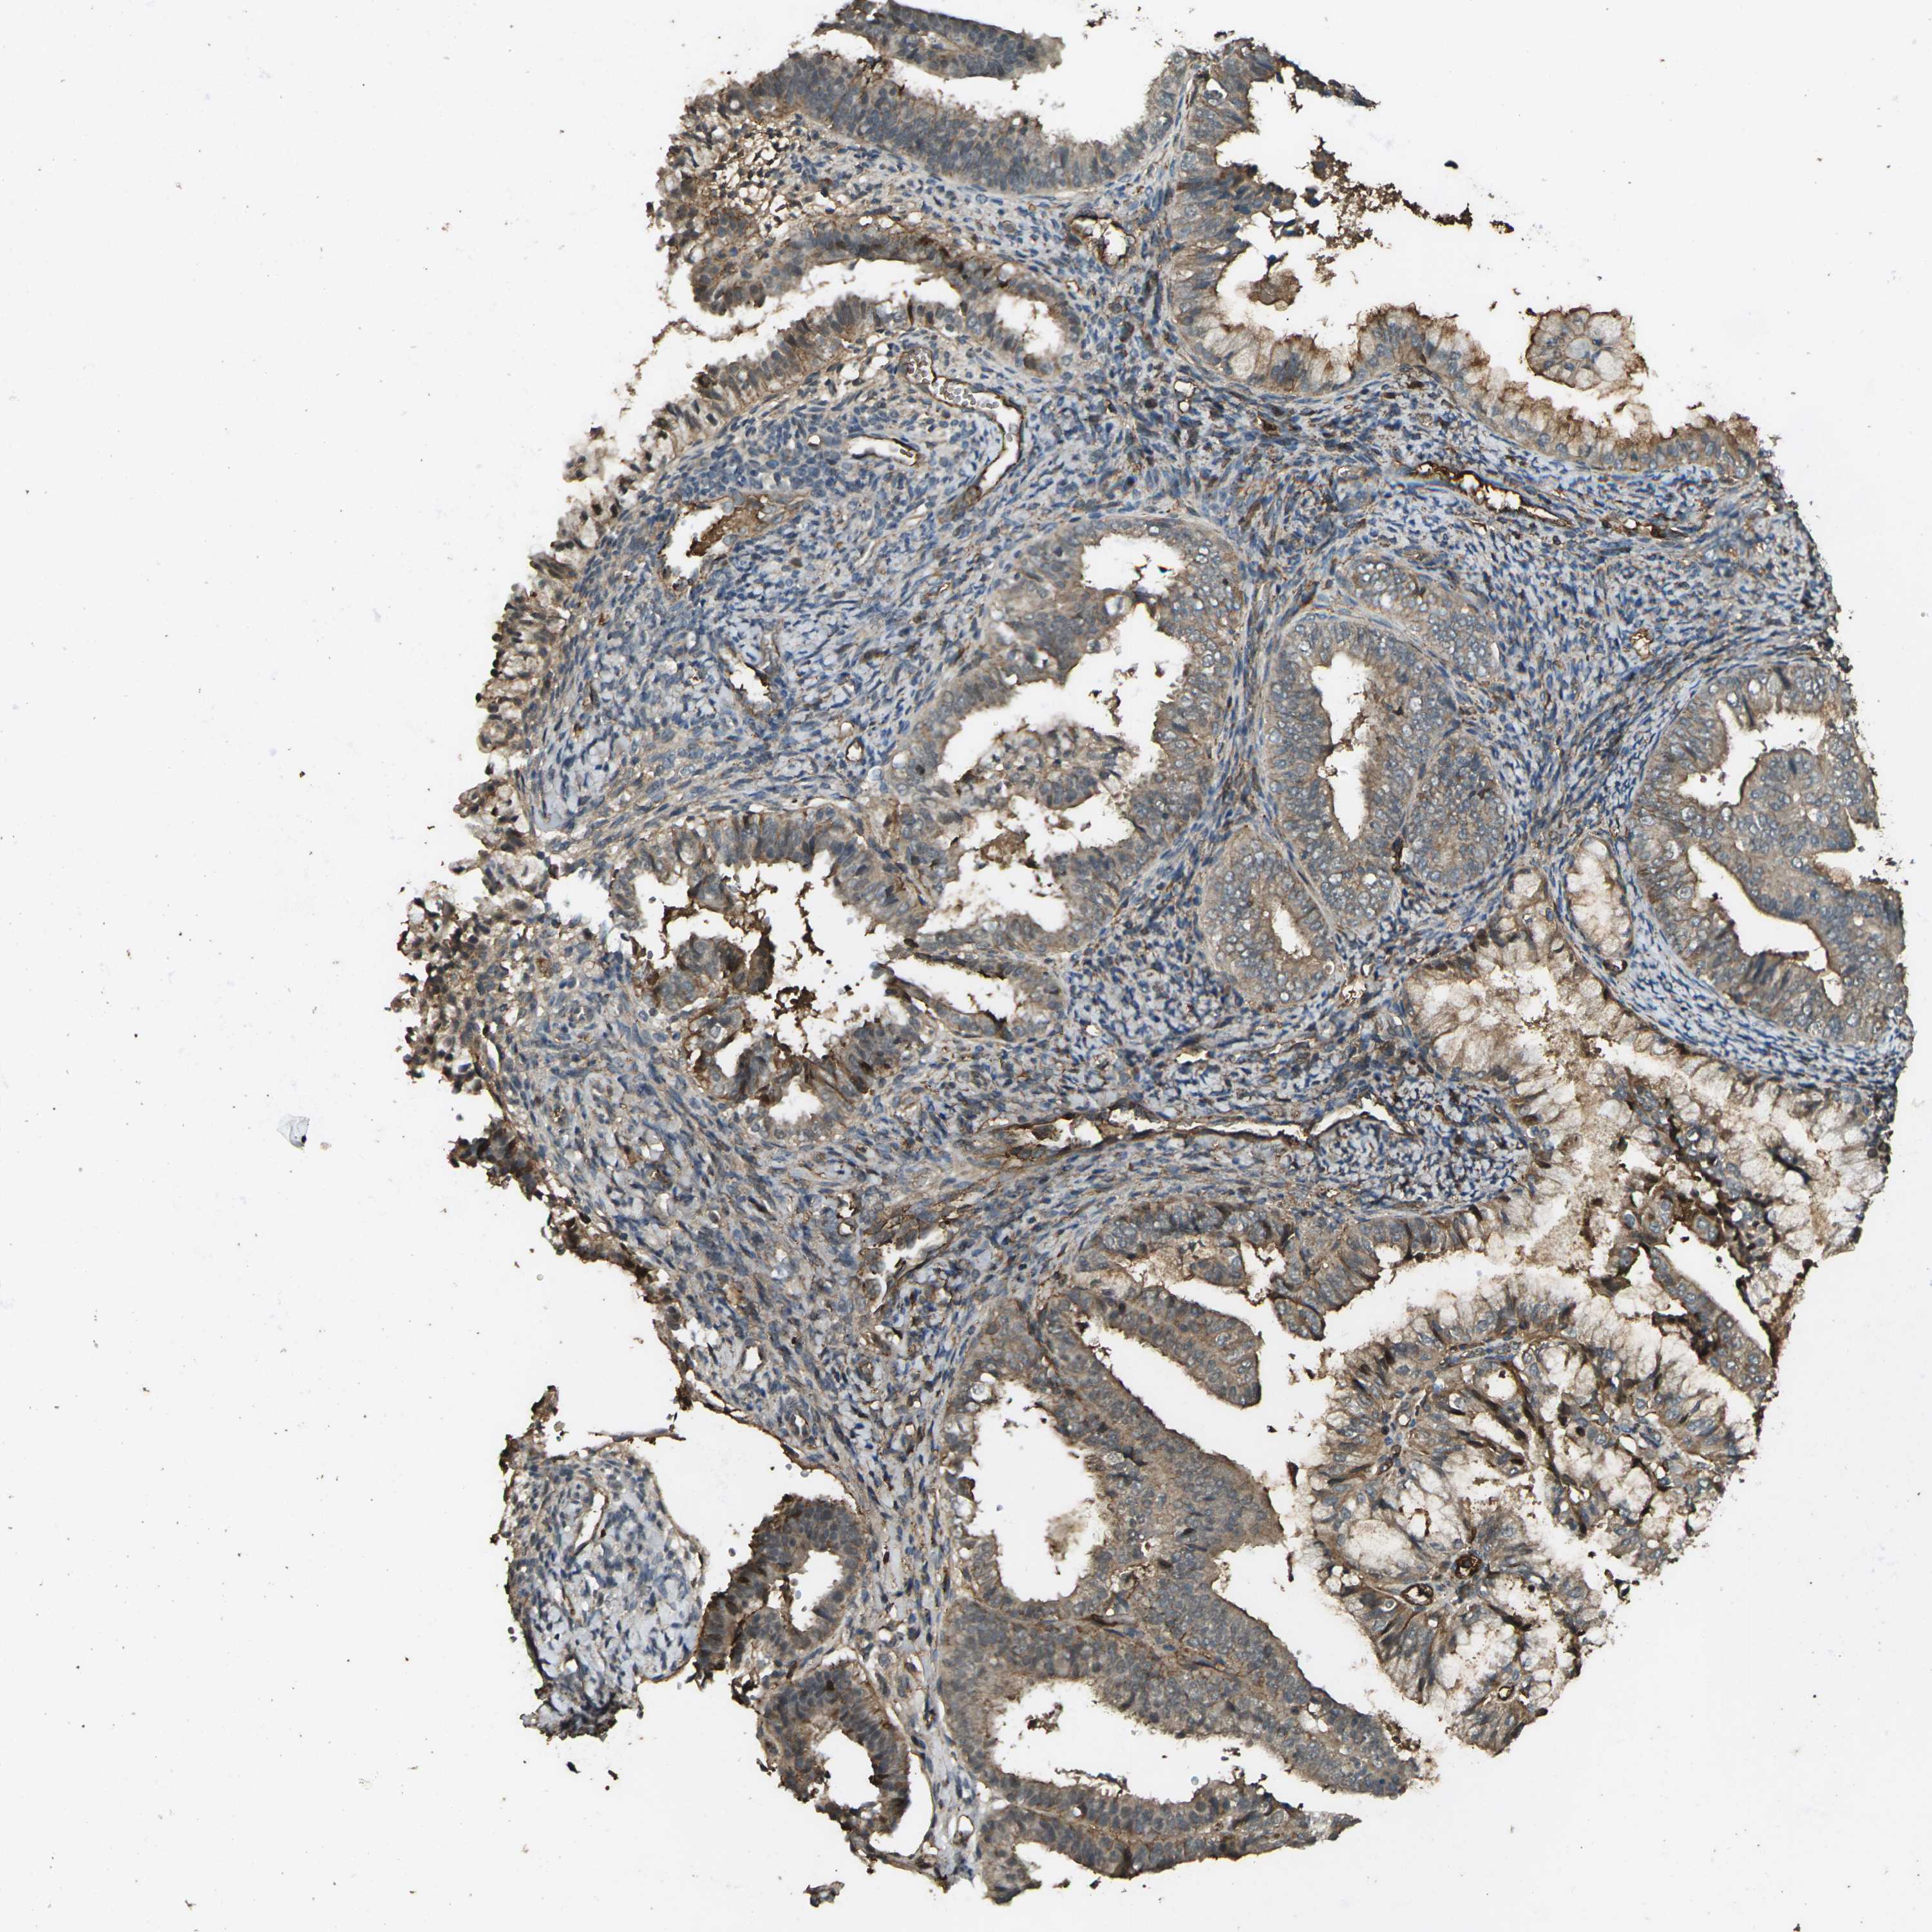

ENDOMETRIAL CANCER - Protein expressioni

A mouse-over function shows sample information and annotation data. Click on an image to view it in a full screen mode. Samples can be filtered based on level of antibody staining by selecting one or several of the following categories: high, medium, low and not detected. The assay and annotation is described here.

Note that samples used for immunohistochemistry by the Human Protein Atlas do not correspond to samples in the TCGA dataset.

Antibody stainingi

Antibody staining in the annotated cell types in the current human tissue is reported as not detected, low, medium, or high, based on conventional immunohistochemistry profiling in selected tissues. This score is based on the combination of the staining intensity and fraction of stained cells.

Each image is clickable and will lead to virtual microscopy that enables deeper exploration of all samples and also displays staining intensity scores, fraction scores and subcellular localization as well as patient and tissue information for each sample.

Antibody HPA026863

Antibody CAB011705

Staining

High

Medium

Low

Not detected

Intensity

Strong

Moderate

Weak

Negative

Quantity

>75%

75%-25%

<25%

None

Location

Nuclear

Cytoplasmic/membranous

Cytoplasmic/membranous,nuclear

Adenocarcinoma, NOS

Adenocarcinoma, metastatic, NOS